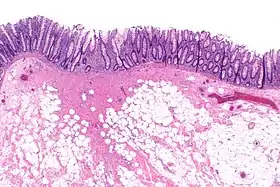

Micrograph showing a colorectal polypectomy scar. H&E stain.